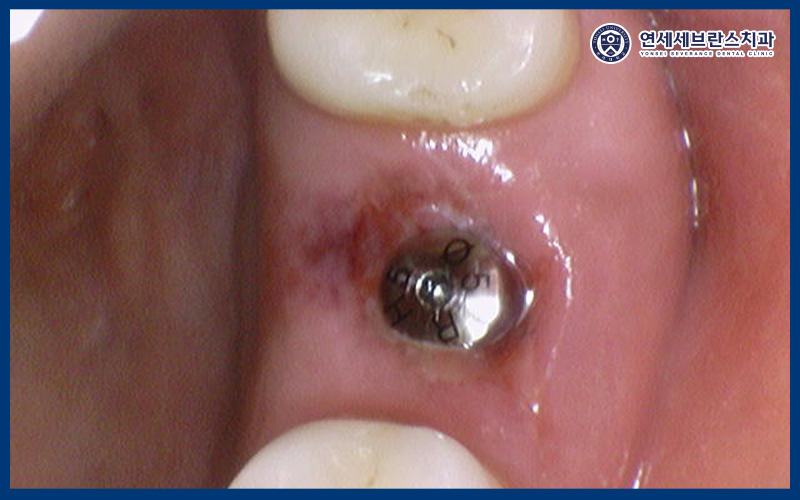

25.07.29

<기존 임플란트 확인>

기존 임플란트를 제거하고 확인해 보았을 때,

염증이나 오염이 확인되지 않아,

바로 재식립을 진행하였습니다.

내부의 오염 가능성이 있기 때문에

정밀하게 확인하였는데,

특별한 문제 없이 깨끗하여 별도의 뼈이식 없이

임플란트를 식립하는 과정을 거쳤답니다.

25.07.30

<수술 후 소독 진행>

이렇게 수술 마무리 후

하루 뒤 내원하셔서

염증이 생기지 않도록

수술 부위를 소독하였습니다.